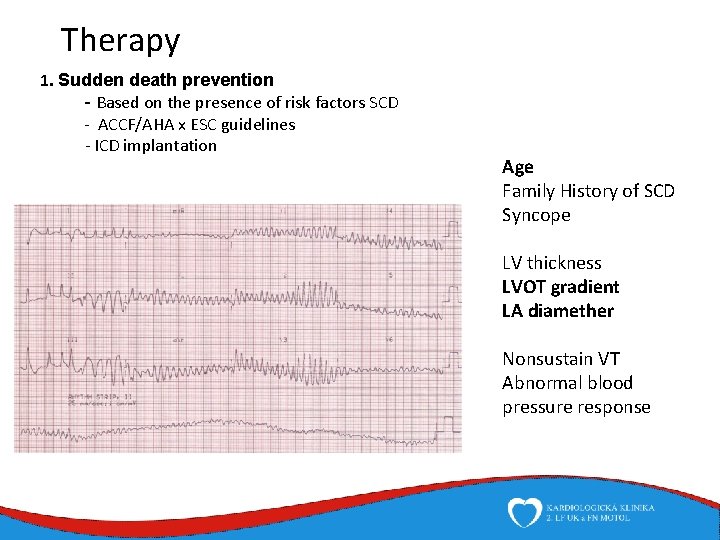

Therapy 1. Sudden death prevention - Based on the presence of risk factors SCD - ACCF/AHA x ESC guidelines - ICD implantation Age Family History of SCD Syncope LV thickness LVOT gradient LA diamether Nonsustain VT Abnormal blood pressure response